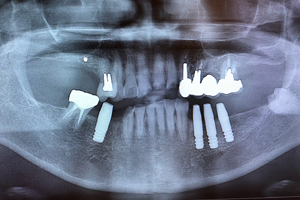

症例4

- 年齢・性別

- 60歳

- 治療期間

- 6ヶ月

- 抜歯

- 残根抜歯のみ

- 治療費

- 198万円

- 備考

- 右上5.6 右下5 左下4.5.6欠損

- 治療内容

- 6本のインプラントを右左側に2回に分けて埋入

- 施術の副作用(リスク)

- オペによる知覚障害。インプラントによる歯肉炎。インプラント脱落。